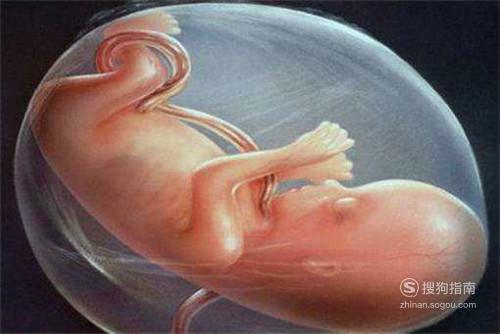

很多女性朋友都有抽烟的习惯,同时有些女性朋友即便在怀孕之后,仍然会保持着这种坏习惯。其实怀孕之后还一直都在抽烟的话,不仅对准妈妈身体有影响,还会给腹中的宝宝带来更大的伤害。那么孕妇抽烟有什么坏处?下面就让我们一起来了解下吧!

胎儿体重过低,通常怀孕期间还在抽烟的朋友,胎儿的体重比起正常的胎儿明显要低很多,这是因为在抽烟的过程中需要许多养分和氧气来替换,很容易就会造成胎儿营养不充分,从而出现体重比较轻的情况。

胎儿畸形,在抽烟的时候,散发出来的烟雾会含有许多有害的物质,比如尼古丁等,这些有害的物质会增加胎儿出现畸形的几率,并且烟碱对胎儿的伤害也特别严重,很有可能出生之后听力会比较差等。

胎儿患支气管炎几率较高,本来吸烟就对身体危害比较大,还有可能会出现肺癌。如果怀孕期间孕妇还一直在抽烟,这样就会间接影响胎儿,很有可能出生之后还会得支气管炎疾病。

早产几率高,怀孕期间孕妇抽烟的害处非常大,除了上面说的那几点,还有可能会出现早产的现象,如果情况严重的话,胎儿还会直接死在腹中,所以一定要小心了。

增加流产几率,如果在怀孕期间依然保持着吸烟的习惯,那么相对正常孕妇来说发生流产的几率要多很多,这是因为在吸烟的过程中对胎盘会有一定的伤害,从而造成流产的现象,因此女性朋友在怀孕的时候,切记要远离抽烟。

胎儿生长缓慢,烟草里面是含有一氧化碳等有害的物质,在抽烟的过程中,会进入到孕妇的血液里面,这样就会导致血氧量出现减少的现象,并且胎盘里面的氧含量也会明显的减少,很容易就出现胎儿缺氧的现象,最终导致胎儿在腹中生长缓慢。

胎儿在宫内发生窒息的几率增高,烟草里面有尼古丁这种毒素,要是怀孕以后还抽烟的话,就会导致胎盘里面的血氧量逐渐偏低,这样就没有办法满足胎儿的生长需求,还会导致胎盘出现增大的现象,滋生出大量的细菌,很容易胎儿就出现窒息的现象。

毕竟已经怀孕了,准妈妈应该远离充满烟味的地方,确实二手烟也会产生伤害,如果家里有抽烟的朋友,为了妈妈和胎儿着想,应该制造出无烟又安全的环境,让宝宝健康成长。